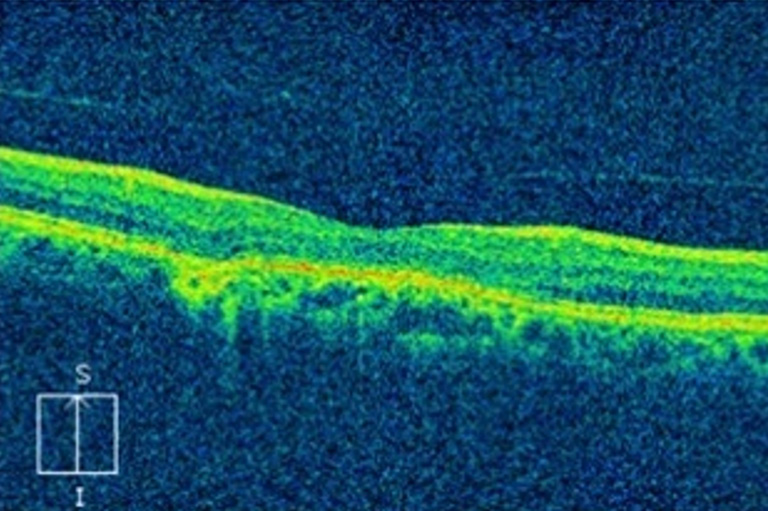

在白内障术眼低视力的患者中,高度近视性脉络膜视网膜病变1 2例(24.5%),椭圆体带连续性破坏1 0例(20.4%),糖尿病性视网膜病变8例(16.3%),黄斑裂孔5例(10.2%),老年性黄斑变性4例(8.1%),黄斑前膜3例(6.1%),黄斑区视网膜厚度变薄1例(2.0%),视网膜色素变性1例(2.0%),视网膜劈裂症1例(2.0%),视网膜分支动脉阻塞1例(2.0%),白塞氏病1例(2.0%),缺血性视神经病变1例(2.0%),视网膜前膜1例(2.0%)。将仅在OCT上发现椭圆体带连续性中断,其他临床检查未发现异常者归类为椭圆体带连续性破坏(图1,图2)。本研究共发现10例患者出现椭圆体带连续性破坏,占20.4%,排在第2位。另外还有1例患者仅在OCT检查上发现黄斑区视网膜厚度变薄,其他检查结果未见明显异常。本组病例有1眼眼底镜下视杯不明显,进行VEP及视野检查,视野检查提示生理盲点扩大,局部暗点,VEP提示P100潜伏期中度延迟,P100振幅轻度下降,结合临床资料,诊断为缺血性视神经病变。

图1 椭圆体带大面积缺失

Figure 1 Large area of ellipsoidal band defect

既往关于白内障术眼低视力的研究

[1-2,7-10,17]多基于人口流行病学调查,检查手段多为常规的眼科检查,如裂隙灯、检眼镜及眼底照相,少部分由于未发现病变而原因未明,约占2.1%~10.4%。本研究引入了具有非接触性、活体视网膜成像特点的OCT检查,进一步了解了白内障术眼低视力的原因。OCT对观察视网膜各层结构的细微变化拥有独特优势,可以清晰地显示视网膜组织显微形态结构的微小病变,比如视网膜各层连续性的改变、轻度视网膜下积液、及玻璃体牵拉等[23-24],这些细微改变也是许多原发性视网膜脉络膜疾病的早期表现。本研究观察到11例患者在常规眼底镜检查下未见明显异常,而通过OCT检查发现其中10例为视网膜椭圆体带连续性破坏,1例为黄斑区视网膜厚度变薄,占22.4%。这些在既往关于白内障术眼低视力原因的研究中均未被发现。椭圆体带在OCT上表现为高反射带,目前认为是由视细胞内节顶端、视细胞外节基底的交界面以及连接视细胞内、外节的连接绒毛复合组成,椭圆体高反射带是观察视细胞是否健在的唯一标志带,一旦椭圆体带有间断、不连续或者缺失,则提示视细胞有损伤性病变[25-28]。研究[25-28]表明:椭圆体带的完整性与视力呈正相关。而椭圆体带的连续性破坏可见于多种疾病,如DR、AMD、视网膜静脉阻塞、黄斑孔、高度近视性脉络膜视网膜病变、视网膜色素变性等[25-32],本研究可观察到类似结果。本研究观察到多种疾病的OCT图像出现椭圆带异常,其中有高度近视性脉络膜视网膜病变9例,DR 5例,AMD 3例,黄斑前膜2例,黄斑孔1例,视网膜劈裂症1例,视网膜分支动脉阻塞1例,视网膜色素变性1例,白塞氏病1例。因此推测这10例仅出现椭圆体带连续性破坏的病例可能处于这些疾病的早期病变阶段。本研究将仅在OCT检查发现视网膜厚度变薄的病例界定为黄斑区视网膜厚度变薄,本组病例中有1例。研究[33-34]表明:视网膜厚度的改变与视功能不良关系密切,视网膜水肿引起的厚度增厚及视网膜萎缩引起的厚度变薄都会导致视力下降。